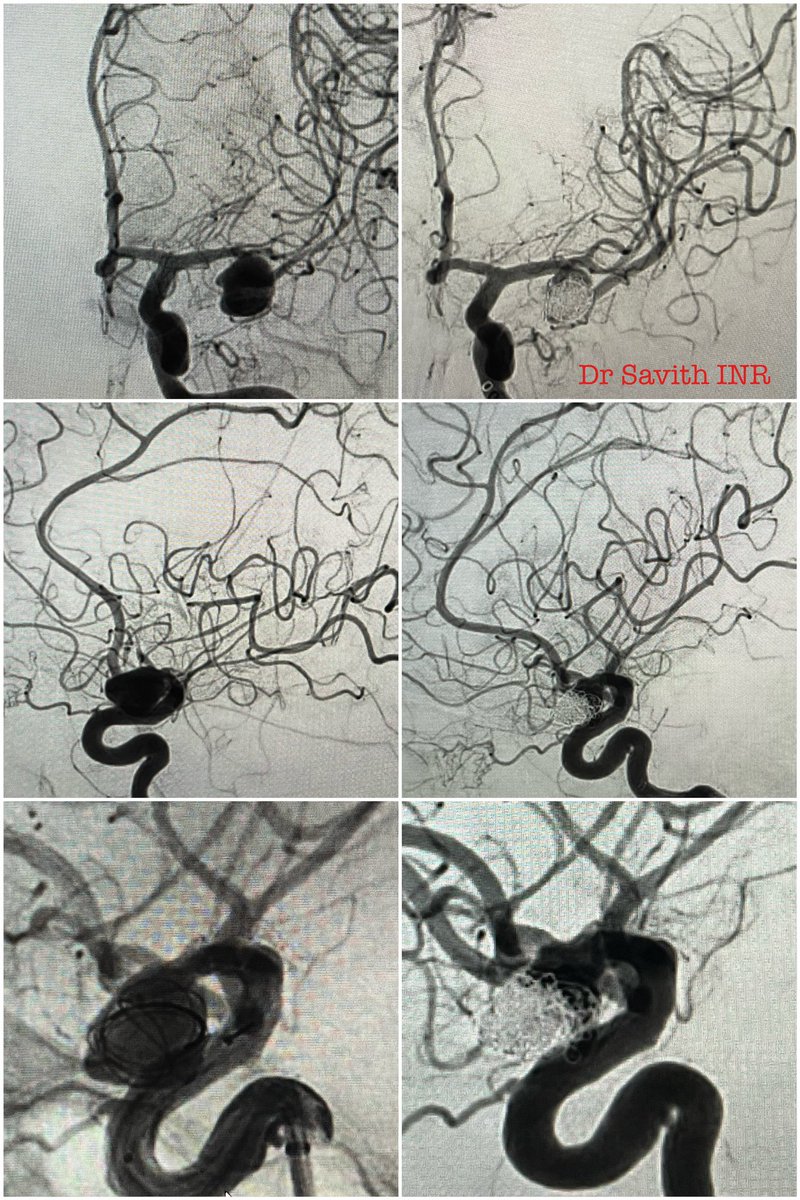

60 year old female with SAH and hydrocephalus from ruptured left PICA dissecting aneurysm. Partent artery occlusion done followed by EVD. Follow up CT showed left PICA territory infarct. Neurological stable. #aneurysm #neurointervention #coiling